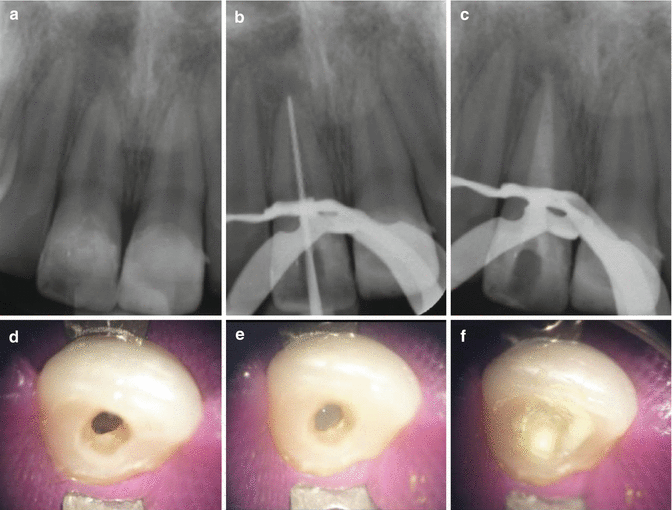

Apexification of the 36. (a) Deep caries reaching the pulp with What Is Apexification In Dentistry Apexification is named after the part of the tooth it treats, the apex, also known as the base of the tooth root. The roots of your teeth extend under the gum and into the jawbone. Apexification is defined as a ‘method to induce calcified barrier in a root with an open apex or the continued apical development of an incomplete.. What Is Apexification In Dentistry.